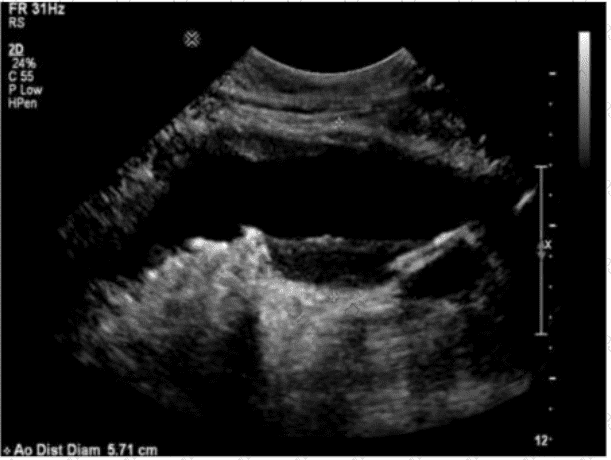

Questions 46

Which action should a sonographer take if the abdominal aorta measures 5.5 centimeters in the anteroposterior diameter?

Options:

A.

Report the finding to the radiologist immediately

B.

Follow the routine protocol for abdominal ultrasound

C.

Release patient from care

D.

Disclose the diagnosis to the patient

Buy Now